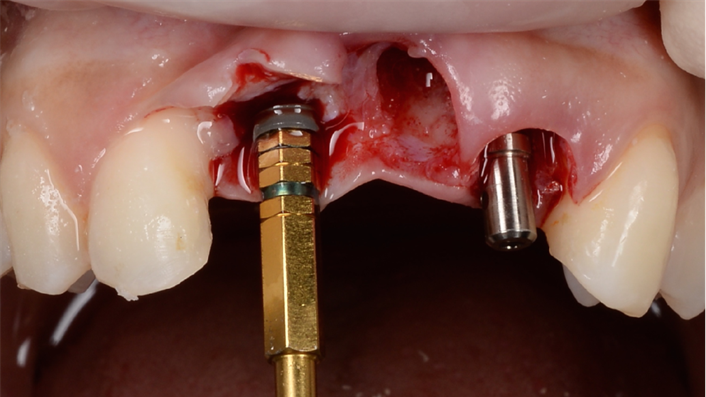

Clinical case: Patient-centered approach: treatment strategy for Root Membrane Technique & delayed implant placement

- Courtesy of Dr. Yoshiharu Hayashi, Japan -

Socket Shield Technique, anterior esthetics, maxillary anterior, esthetic, esthetics, delayed implant placement, socket preservation, AnyRidge, Root Membrane Kit, Root Membrane Technique, Partial Extraction Therapy, PET, esthetic zone, fuse abutment, Dr. Yoshiharu Hayashi,#11,#21,#22

AnyRidge implant system, fuse abutment Root membrane kit, PET Kit